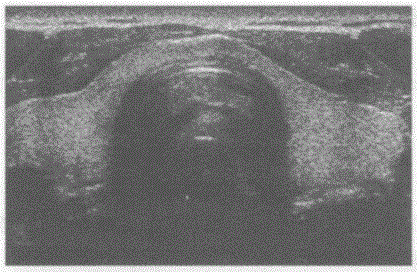

问题 请回答下图是采用何种切面扫查获取的颈部哪一部位声像图:

选项 A.甲状腺横切扫查 B.甲状腺纵切扫查 C.颌下腺横切扫查 D.腮腺纵切扫查

答案 A